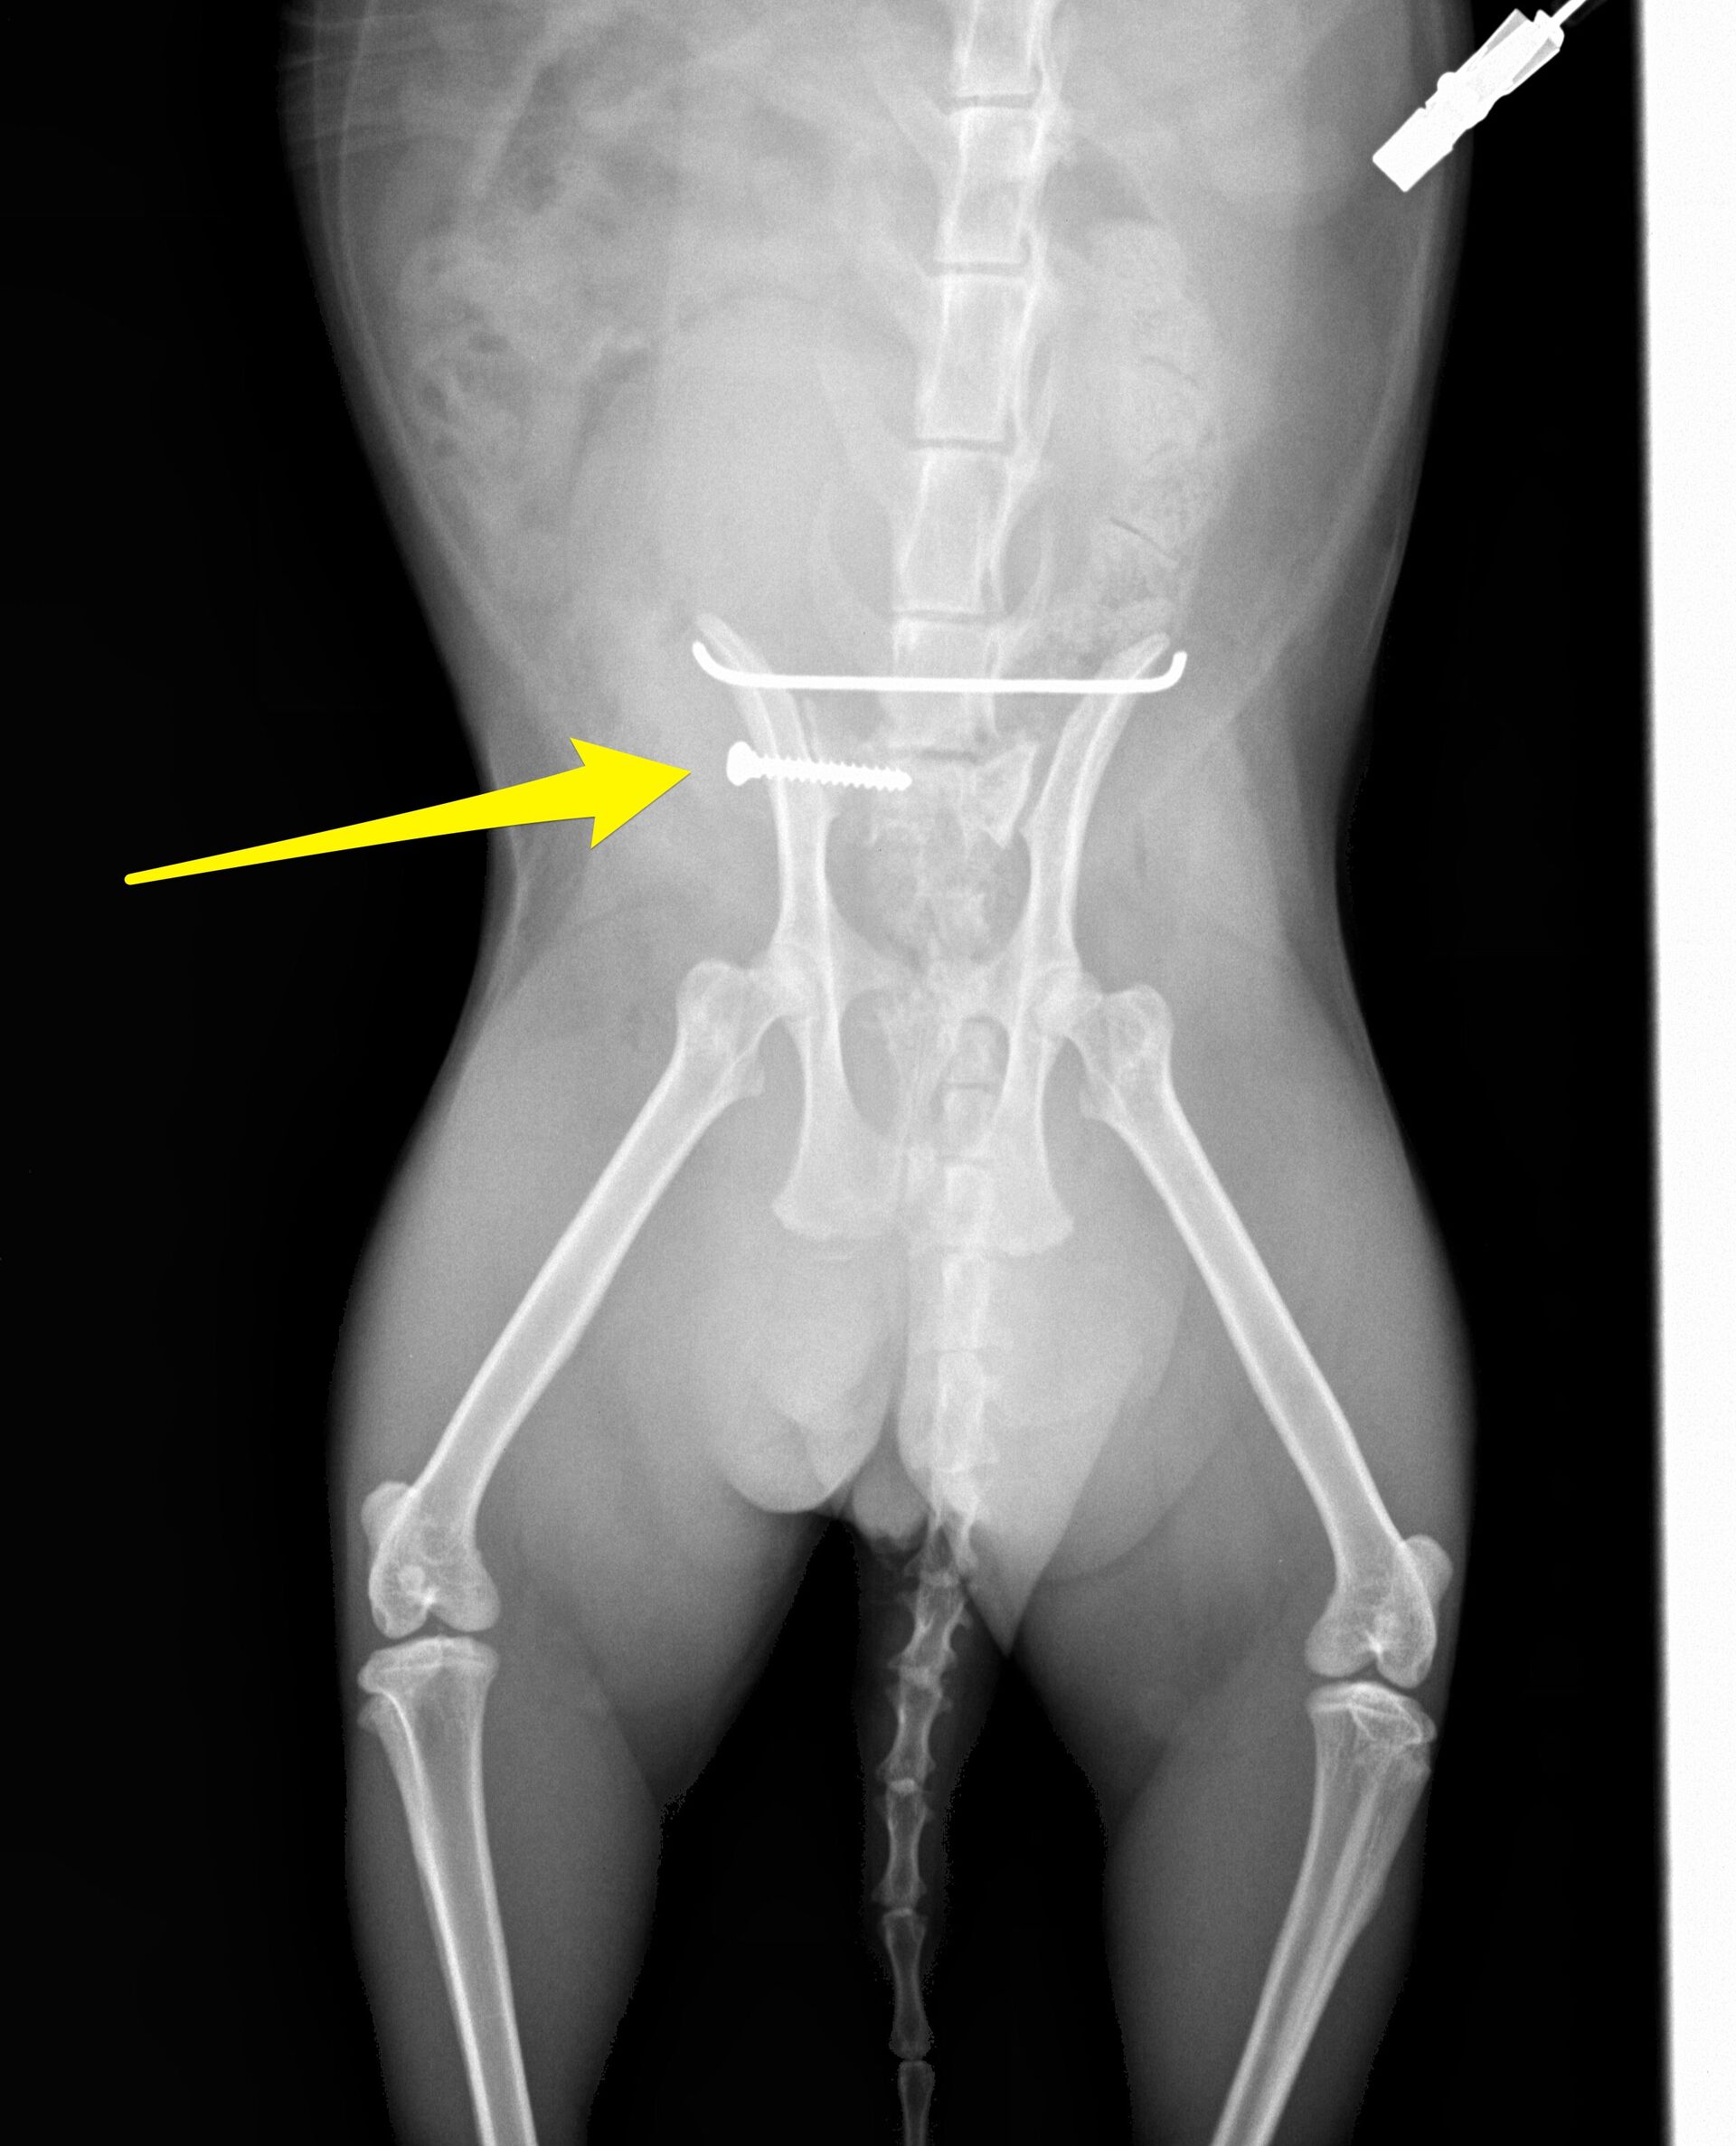

下の写真が手術後です。

仙腸関節はスクリューで固定し(黄色矢印)、それだけでは回転してしまうので、腸骨同士をピンで固定しています。

その後、2ヶ月後にスクリューとピンを除去する手術をして、

今は以前と変わりなく、外にも遊びに行っているそうです。